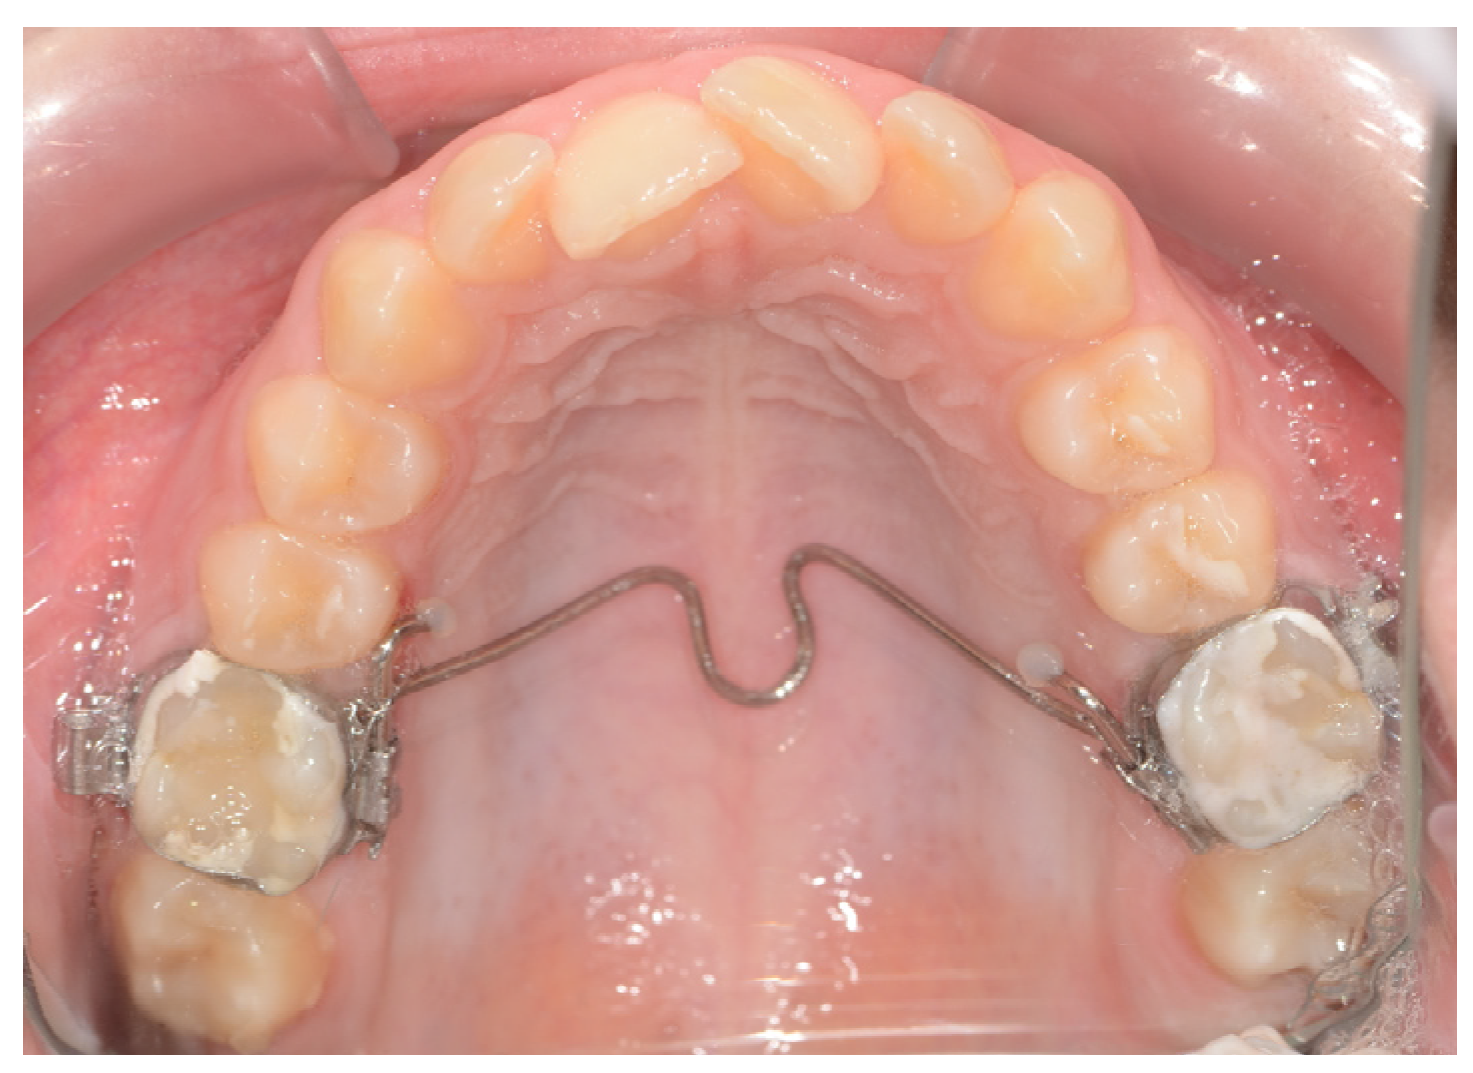

4.1.5. Distal Jet Appliance

4.1.14. Keles Slider Appliance